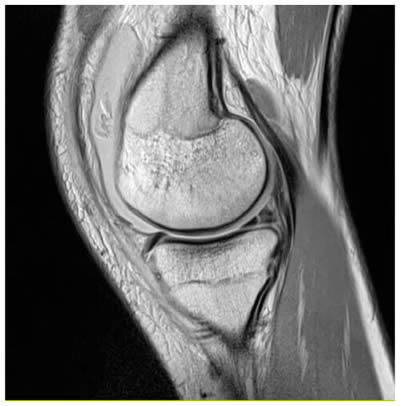

Le ménisque normal

Dessin d'un ménisque normal, vu du dessus

Menisque normal, sous arthroscopie.